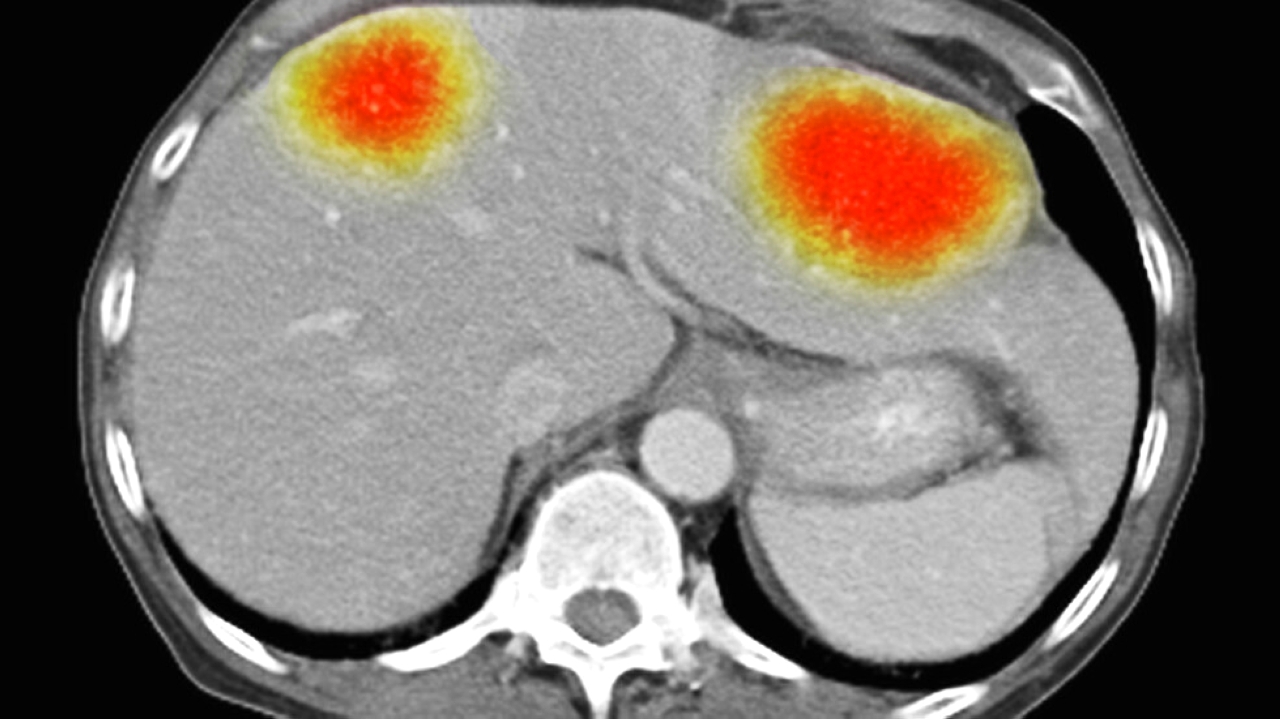

تمكن باحثون من استخدام جزيئات صغيرة من الذهب، مشحونة كهربائياً، لخداع الخلايا في أحد أكثر أنواع السرطان فتكاً كي تقوم بتدمير نفسها، ويأمل هؤلاء أن يصبح العلاج متاحاً يوماً ما على شكل رذاذ.

وقام فريق العلماء، من جامعة نوتنغهام، بقيادة د. فرانكي روسون، على ما أفاد تقرير نشره موقع «روسيا اليوم»، بتسخير قوة bio-antenna تميت الخلايا بشكل مبرمج، (خلايا الورم الأرومي الدبقي).

ويزعم العلماء أن هذا هو أول نهج علاجي كمي، يُظهر أنه يمكن القضاء على السرطان عن طريق إجراء تغييرات في بيولوجيا الخلايا على المستوى الكمي.